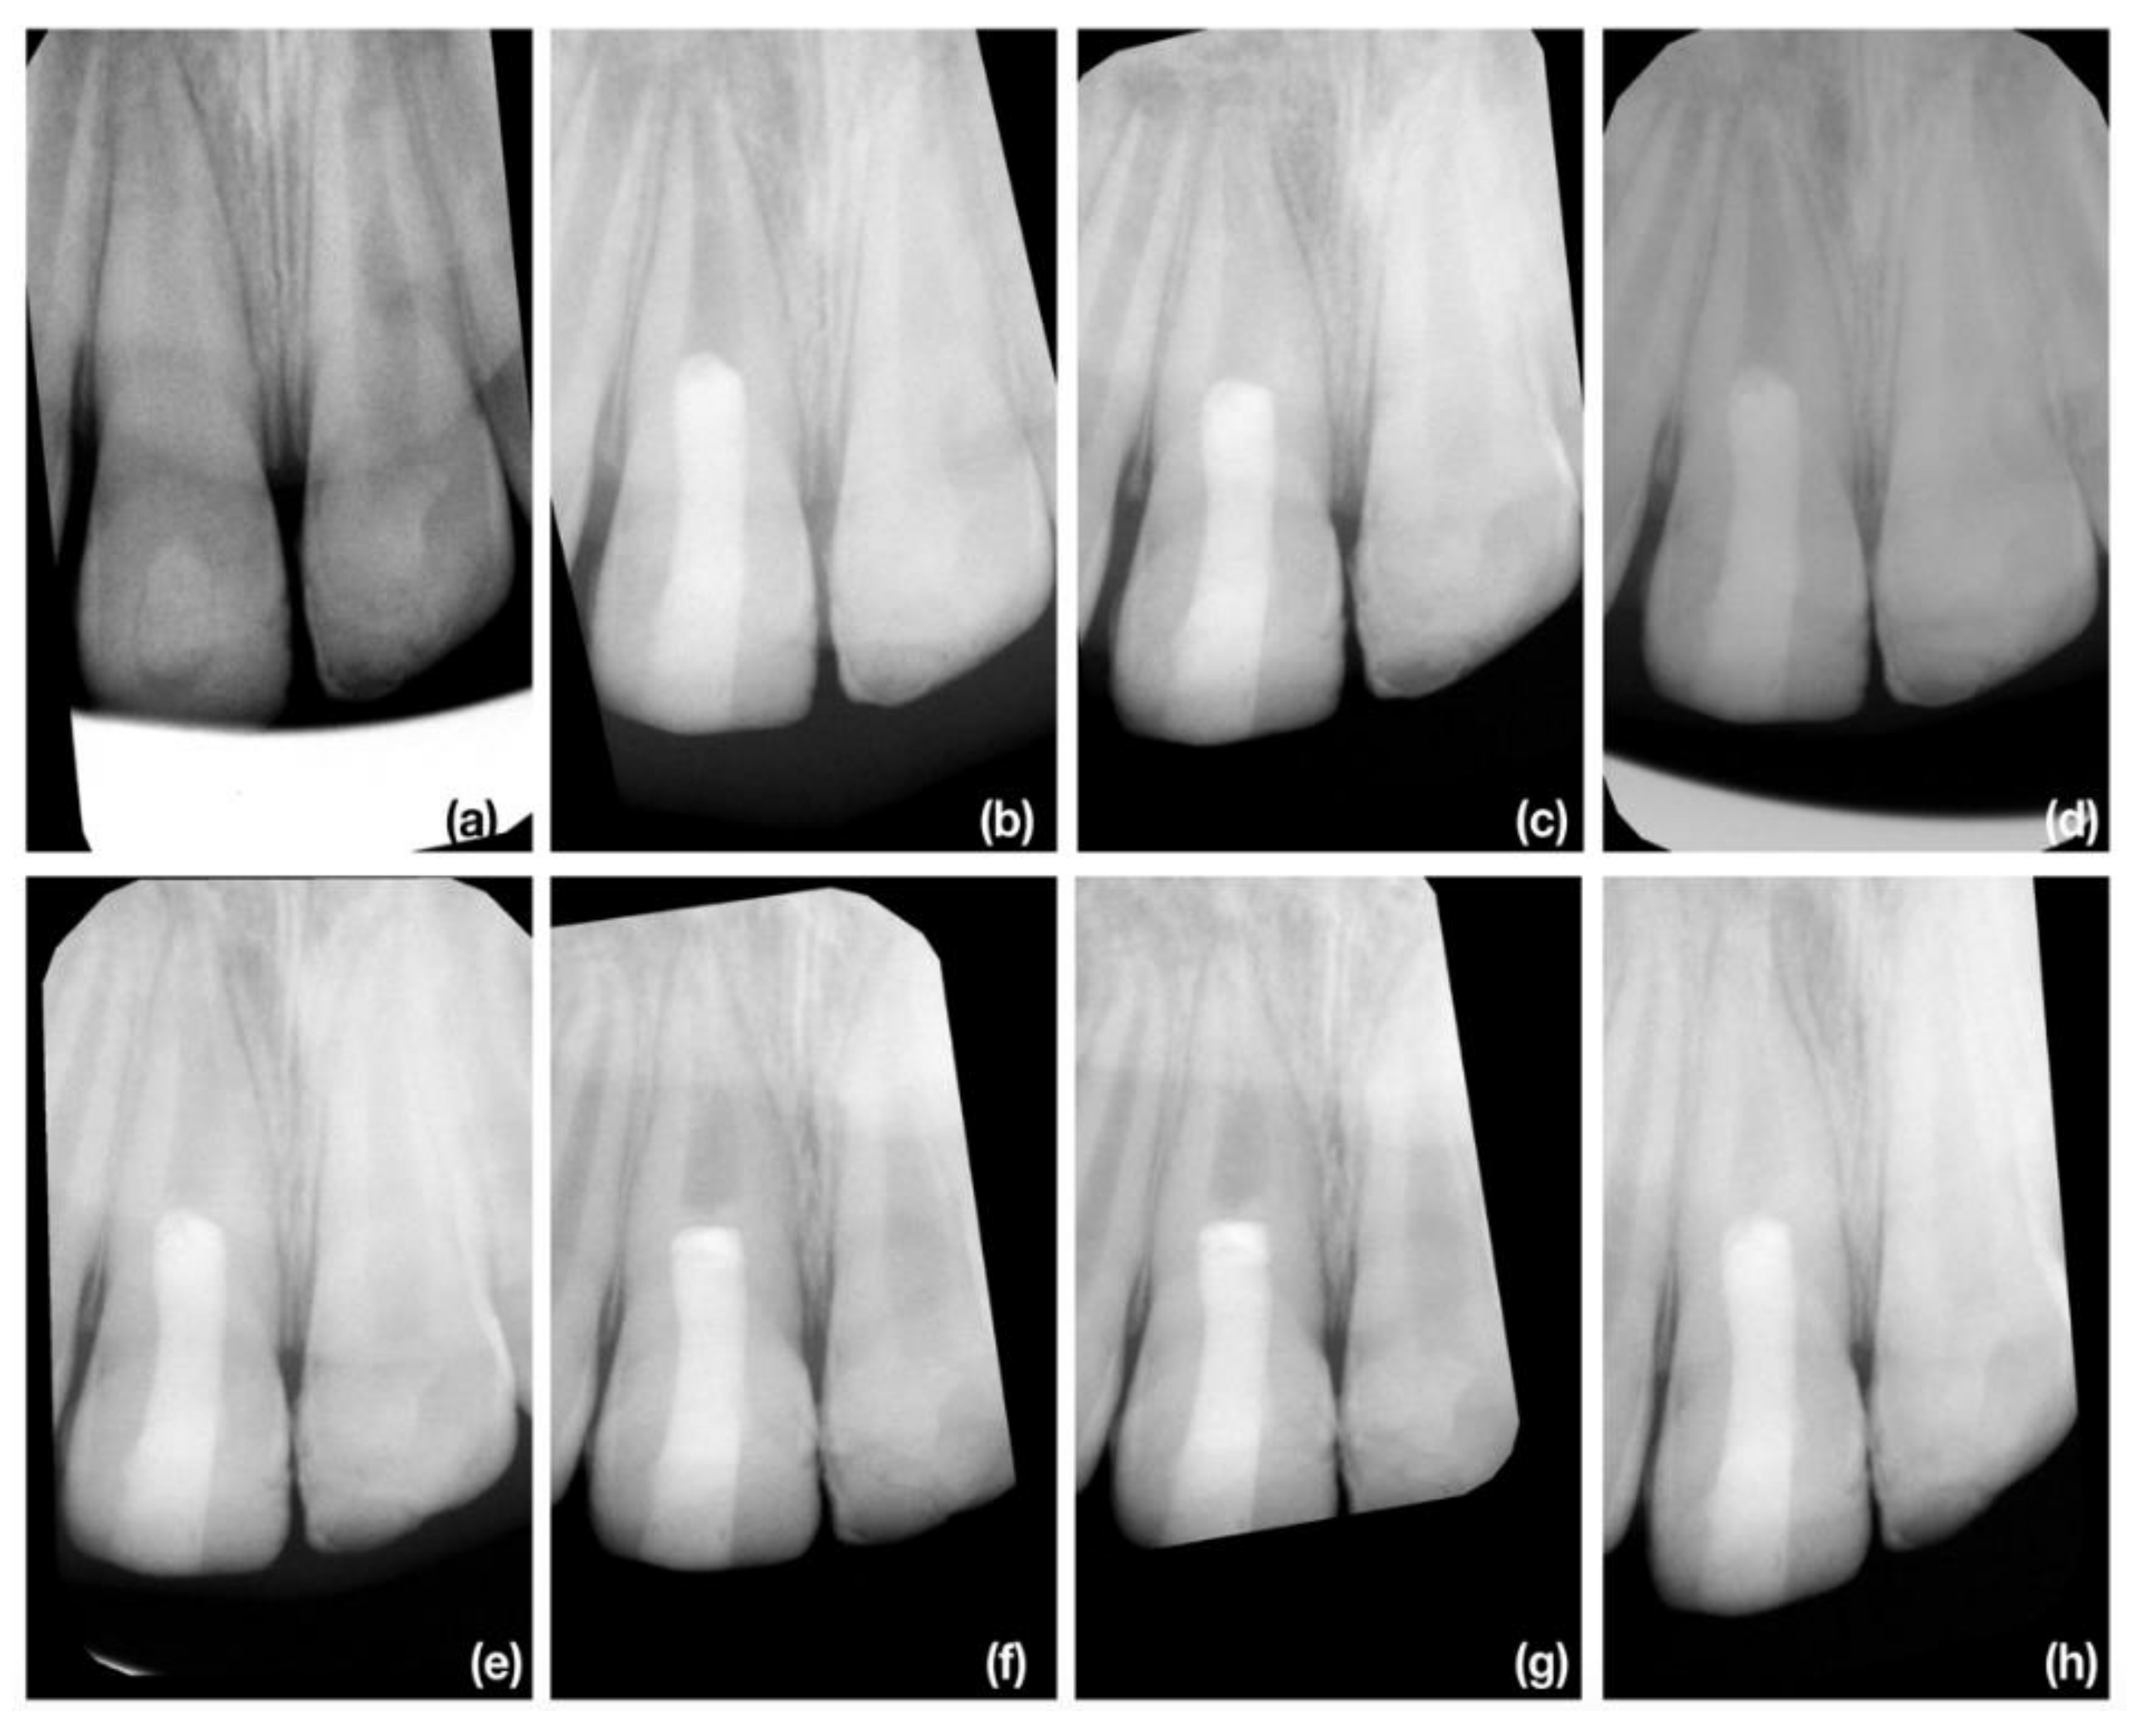

2.4. Radiographic Assesment

2.4.2. Radiographic Root Length Measurement

2.4.3. Radiographic Root Width Measurement

2.4.4. Radiographic Root Area Measurement

3.2. Radiographic Root Length Change

3.3. Radiographic Root Width Change

3.4. Radiographic Root Area Change

3.5. Discoloration

3.6. Periapical Index Change